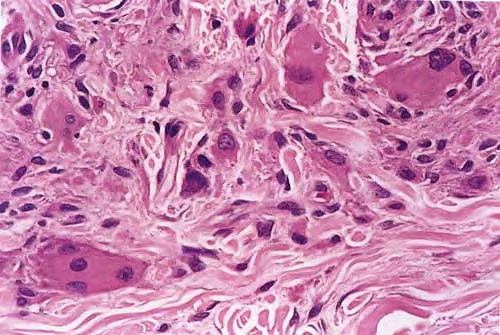

Multicentric reticulo histiocytosis = داء كثرة الناسجات الشبكي متعدد المراكز